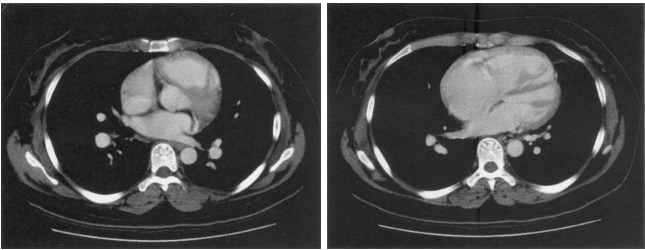

51 16 歲女性,因心雜音就診,注射對比劑後 CT 影像如附圖,則最可能的診斷為下列何者?

(A) Sinus venosus type atrial septal defect (B) Membranous type ventricular septal defect (C) Outlet type ventricular septal defect (D) Secundum type atrial septal defect